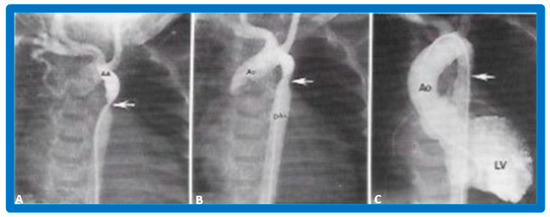

3.4. Aortic Coarctation, Postsurgical

4.4. Aortic Coarctation, Postsurgical

5.4. Aortic Coarctation, Postsurgical